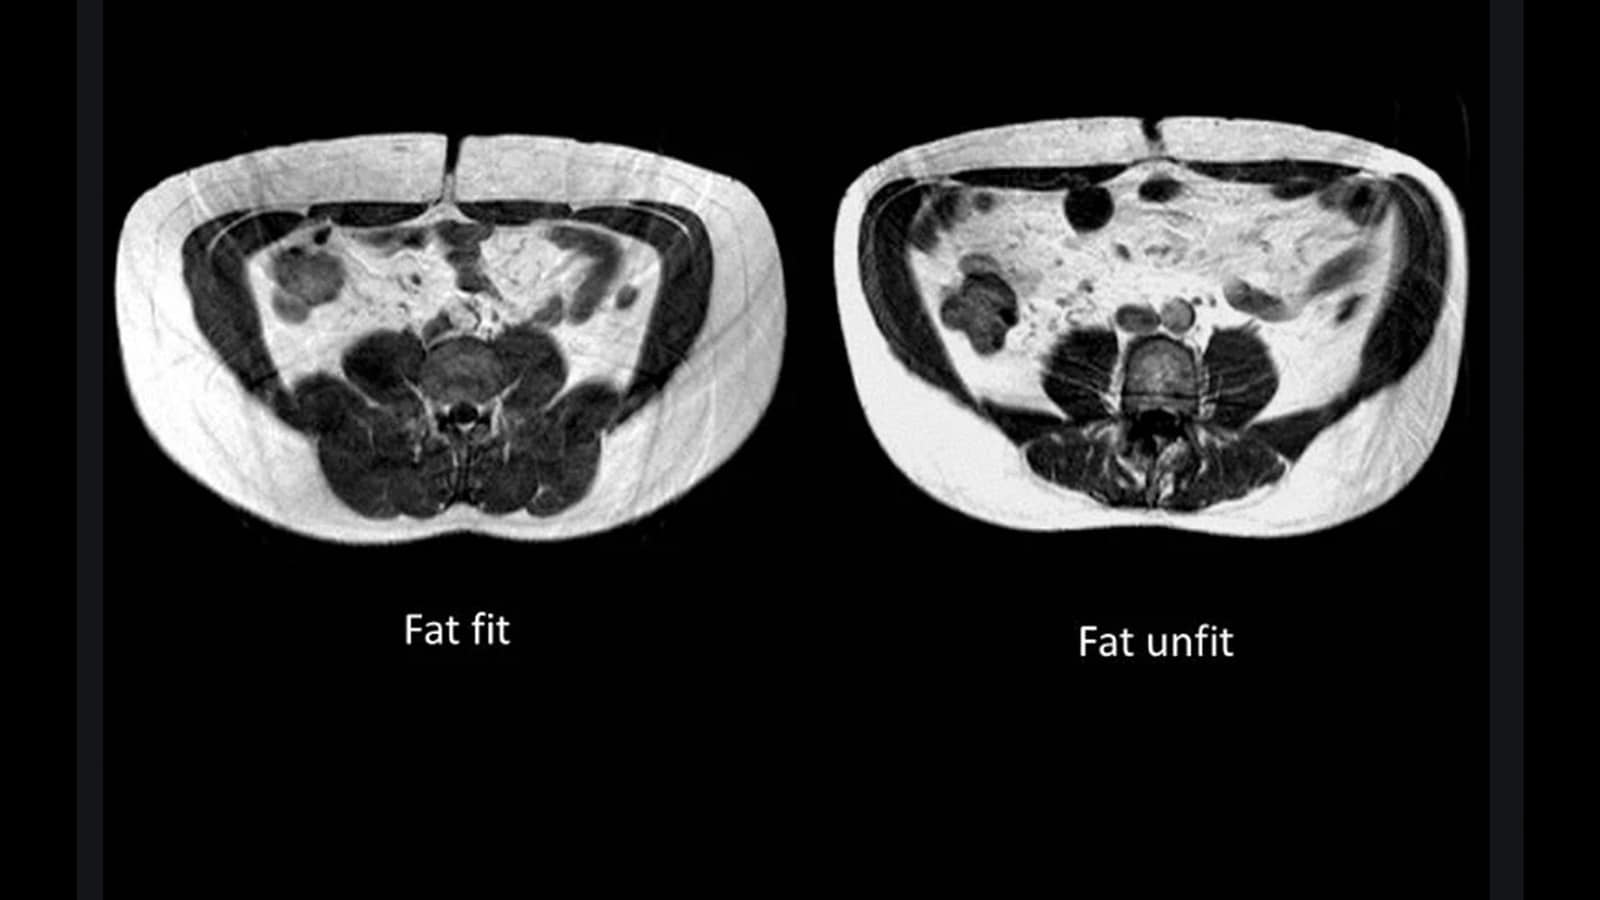

Dann mal nur ein (einer von vielen) Ansatz, ein besserer Mensch zu werden... Informier Dich doch mal über TOFIs:

Menschen, die nach außen hin schlank wirken, aber sehr verfettete Organe haben.

Rechtes Bildle...

Bild

Woher kommt sowas? Genauso wie bei den Altmaiers unter uns... vor allem Genetik, aber auch schlechte Ernährung (v.a. industriell hoch verarbeiteter Zucker) und Bewegungsmangel. Aber: viel gefährlicher für die Gesundheit als ein rein optischer Bierbauch (linkes Bild).

Also, wenn Du das nächste mal Heiko Maas im Fernsehen siehst, fehlen Dir vielleicht einfach ein paar Informationen über seine Gesundheit als die Schnelldiagnose des geschätzten Taillenumfangs liefern kann.

Es gibt 2 Arten von Fett.

Subkutanes und viszerales.

Das subkutane (äußere) Fett soll nicht ganz so schädlich sein wie das viszerale (innere). Das Viszerale fühlt sich von außen hart und relativ fest an während das subkutane weich und schwabbelig ist. Das innere ist gefährlicher da es die inneren Organe verfettet

von daher